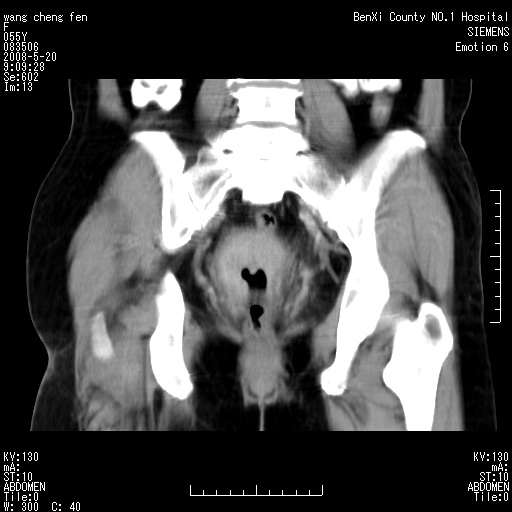

女、绝经后阴道流血3个月

宫颈好像也有问题吧,大家在仔细看看,另外彩超回报为卵巢占位。建议ct。

支持浆膜下子宫肌瘤.之前由于网络原因未看全图片,现在重看,宫颈见一类圆形低密度影,增强轻度强化,低于肌层强化,宫腔扩大,考虑宫颈癌伴宫腔积液可能性大.

1,宫颈部占位,宫颈癌?2,左侧附件区囊实性占位,界较清,实质部分强化明显。考虑浆膜下或阔韧带肌瘤囊变可能大。囊腺类肿瘤不除外。